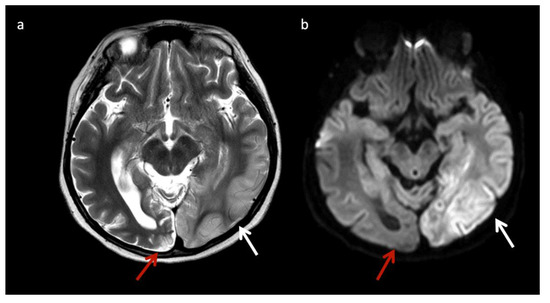

Urea Cycle disorders (Figure 2): Urea cycle disorders (UCD) are caused by defects in the conversion of ammonia to urea, resulting in accumulation of ammonia and glutamine (Gln). Gln is osmotically active, leading to diffuse edema in the cerebral cortex and subcortical white matter when in large concentrations. Brain MR findings characteristic to UCD-related hyperammonemia include a central pattern of edema involving the peri-rolandic, peri-insular, and basal ganglia regions, often sparing the thalami, which helps distinguish it from HIE [3,7,8].

Figure 2.

Example of hyperammonemia induced brain injury, as can be seen with urea cycle disorders. (a) Axial T2 and (b) axial diffusion weighted imaging (DWI) at the level of the basal ganglia show the typical pattern of hyperammonemic central brain involvement with perisylvian, periinsular, and basal ganglia signal hyperintensity consistent with mixed vasogenic and cytotoxic (white arrows, b) edema. (c) Single voxel (SV) short TE MRS demonstrates increased glutamine and glutamate (glx) with overlapping peaks at 2–2.5 ppm (2.4 ppm peak corresponds to elevated glutamine) and an elevated peak at 3.8 ppm consistent with glx associated alpha protons (glx-a). Lac and Cr are also elevated while Cho is depressed.

MRS shows elevated Glu/Gln peaks between 2 and 2.5 ppm during times of hyperammonemia, and a lactate doublet at 1.3 ppm when mitochondrial function fails to meet metabolic demand [3]. Glu/Gln resonances overlap at 1.5T but are more separable at 3T due to chemical shift dispersion; the peak centered at 2.4 corresponds more to glutamine [16]. There is also a commonly overlooked glx peak produced by alpha protons at 3.75 ppm. MI and Cho are usually reduced in chronic hyperammonemia, findings that can be highly suggestive of an underlying UCD in the correct clinical context [6,17].